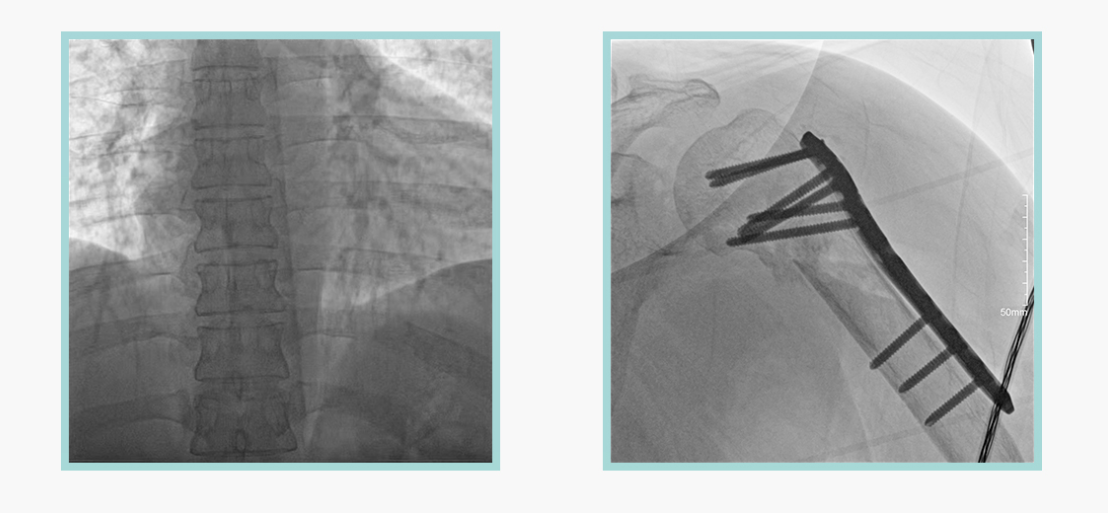

作为全球X线机的主要参与者,ty8天游平台登录科技在数字化X线产品线实现全线动态化之外,在移动C臂X光机产品线领域推出全新平板移动C臂产品:悦画。随着国家“千县工程”提升基层医疗卫生服务能力,外科对于手术介入引导设备的需求剧增。对于一台优秀的移动C臂X线机而言,如何保证最优质影像的同时,最大程度降低X线的辐射剂量,并在满足临床手术引导/定位的同时,最大程度的保护临床手术的医务人员,是悦画最为关切的问题。

此外,骨科手术时间平均时长约为45分钟左右时间,长期的X线透视或摄影曝光剂量将对临床手术与操作医务工作者造成难以评估的健康风险,悦画通过支持摄影曝光参数的自主调节,可以保证在最低剂量水平下输出满足临床手术定位与引导所需要的影像质量,相较于市面上的固定曝光参数配置移动C臂,自主参数调节设计的曝光功能设计,可以大幅减少医务工作者的X线辐射剂量。

不仅如此,悦画在产品的剂量安全管理上,还支持DAP剂量实时显示与统计功能。为了减少误操作的X射线曝光,悦画具有X射线锁定保护功能,在摄影曝光停止后立即进行X射线曝光锁定,解锁后才能支持继续曝光,减少以往临床过程中医务工作者因为误操作所导致的额外X射线辐射。